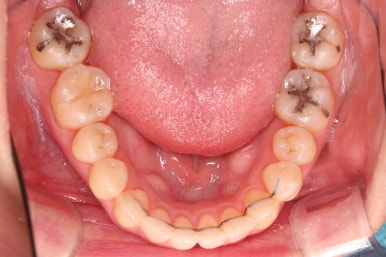

1년 2개월이라는 비교적 짧은 기간안에 원하시는 부분을 깔끔하게 개선했습니다.

전후 비교해 볼게요.

이번 환자분도 삐뚤한 치열을 비발치로,심지어 미니스크류 사용도 없었고 치간삭제도 거의 하지 않았는데요.

입이 나오거나 뻐뜨러지는 느낌 전혀 없죠?

진료 메카니즘을 잘 구성하고 철사를 잘 다뤄주면 좋은 결과를 얻을 수 있답니다.